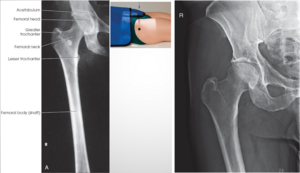

AP Femur

A

• IR 14x17 lengthwise (portrait), 40 SID

• Pt supine with femur centered to midline of table or stretcher. Rotate leg internal 5º for distal femur and 15-20º for proximal femur. Condyles should be parallel to IR even if proximal or distal. Ensure knee joint is included on IR (2” of knee joint).

• CR perpendicular to IR and femur, direct to midpoint of IR. Overlap 2-3” of shaft. Marker placed lateral, in thinnest area of ST shadow

Q

Lateral Femur

• IR 14x17 portrait, 40 SID

• Pt in lateral recumbent on affected side (supine if x-table is performed). Flex knee 45º, pt on affected side. Align femur to midline of table or IR. Place unaffected leg behind patient.

• CR perpendicular to femur and directed to midpoint of IR

Adjust IR to include 2” of knee joint. Collimate on both sides. MARKER ANTERIOR FOR LATERAL

AP Hip

• IR 10x12, 40 SID

• Pt supine, arms by side or on chest. Locate femoral neck and align to CR and midline of table/IR. Ensure no rotation of pelvis (palpate ASIS). Rotate affected leg 15-20º internally. Suspend respiration.

• CR perpendicular to femoral neck (femoral neck 1-2” medial & 3-4” distal to ASIS). 2 sided collimation at least.